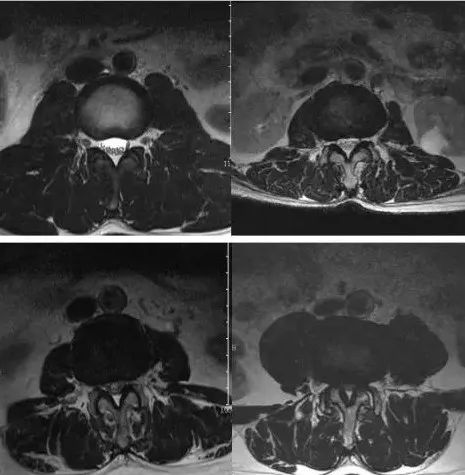

马尾神经沉降征阴性和阳性的 MRI 表现

左图:女性,56 岁,体格检查健康,无明显腰部和下肢不适,腰椎 MRI 横断面 T2WI 图像显示神经根都位于椎管的背侧,表现为马尾沉降征阴性;

右图:女性,62 岁,间歇性跛行 1 年余,MRI 横断面 T2WI 图像显示椎管狭窄,黄韧带肥厚,马尾神经悬浮于椎管内,部分神经根位于椎管腹侧,表现为马尾沉降征阳性